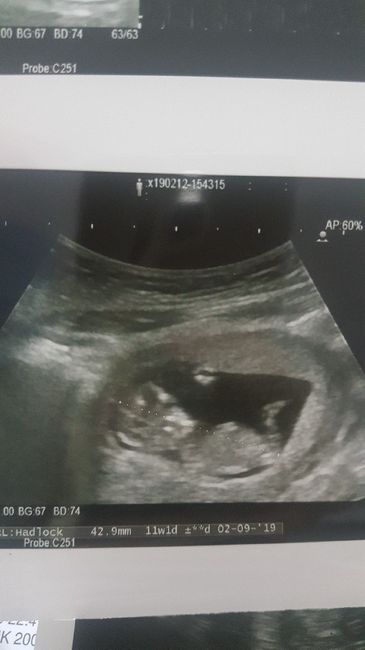

Ciaooo qualcuna ha sentito parlare del metodo Ramzi? A voi ci ha azzeccato o ha sbagliato? Vi metto una foto dell’eco interna a 7+3 “dovrebbe” essere maschio secondo la teoria o sbaglio io a vedere?

Ciao a tutte!Mi interessa e intriga molto questo metodo perciò partecipo anch'io all'indovina il sesso. 😂 In questa eco ero a 11 settimane, ora sono a 13+1. Chi si sbilancia sul sesso?😂

Si delle 11 settimane ho solo questa in cui avevo provato anch'io ad usare la nub theory ma non si vede nulla. Altrimenti ho questa in cui ero a circa 9 settimane

Ciao cara! Hai solo questa?? A 11 settimane si può iniziare a dedurre con la nub theory!